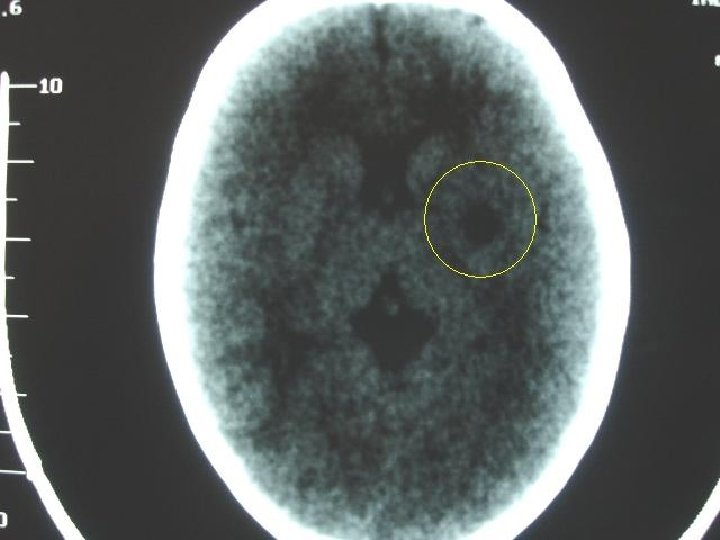

Exames complementares § Hemograma (30/03/05): Ht: 31, 3%; Hg: 10, 4 g/dl; Hm: 3. 960. 000; Leu: 8. 800 (seg: 39%, bas: 0%, linf: 48%, mono: 6%, eos: 7%); plaq: 305. 000. § VHS: 10 mm na 1ª hora. § Bioquímica: GL: 111 mg%; Ca: 10, 2 mmol/l; TGO: 30 U/l; TGP: 14 U/l; Na: 137 m. Eq/l; K: 5, 1 m. Eq/l; Cl: 108 m. Eq/l § TC de crânio (30/03/05): Hipodensidade em território da ACM esquerda sugestiva de AVC(i)

AVC isquêmico § Focal: reducão ou cessação do fluxo sangüíneo para uma área localizada do cérebro devido a oclusão trombótica ou embólica de uma artéria calibrosa ou vasculite de arteríolas. § Global: redução generalizada da perfusão cerebral por parada cardíaca, choque ou hipotensão grave.

AVC em território de ACM § Início abrupto, produz alterações neurológicas como: fraqueza contralateral da face-mão hemiplégica ou sensitivo-motora. Quando afeta o hemisfério dominante tendem a causar afasia, enquanto as que se situam no hemisfério nãodominante tendem a causar estados confusionais, desorientação espacial e diversos graus de indiferença emocional e sensitiva.